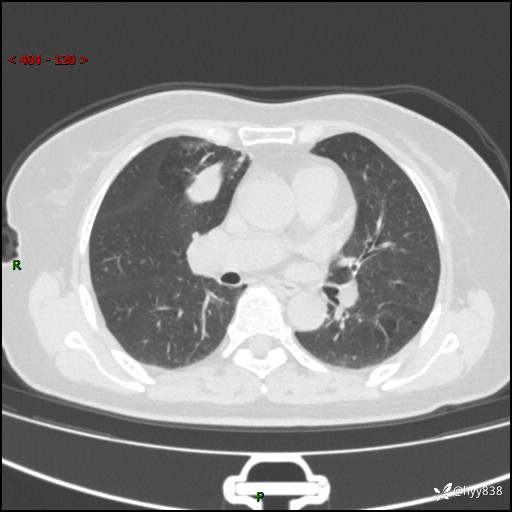

70岁/女,发现右上肺肿物10天。患者过敏体质,只有平扫,错过了一定可惜---结果公布~

【患者信息】:70岁/女

【主诉】:发现右上肺肿物10天

【现病史及既往史】:者10天前因“背部酸痛”于当地治疗,无发热,无呕吐,无头痛头晕等不适,胸部CT示右上肺肿物。遂来我科就诊,门诊看过病人后以“”收入我科, 自患病以来,精神、饮食、睡眠尚可,大小便正常,体力体重无明显减轻。

【检查】:胸部CT平扫(患者过敏体质,不能增强)